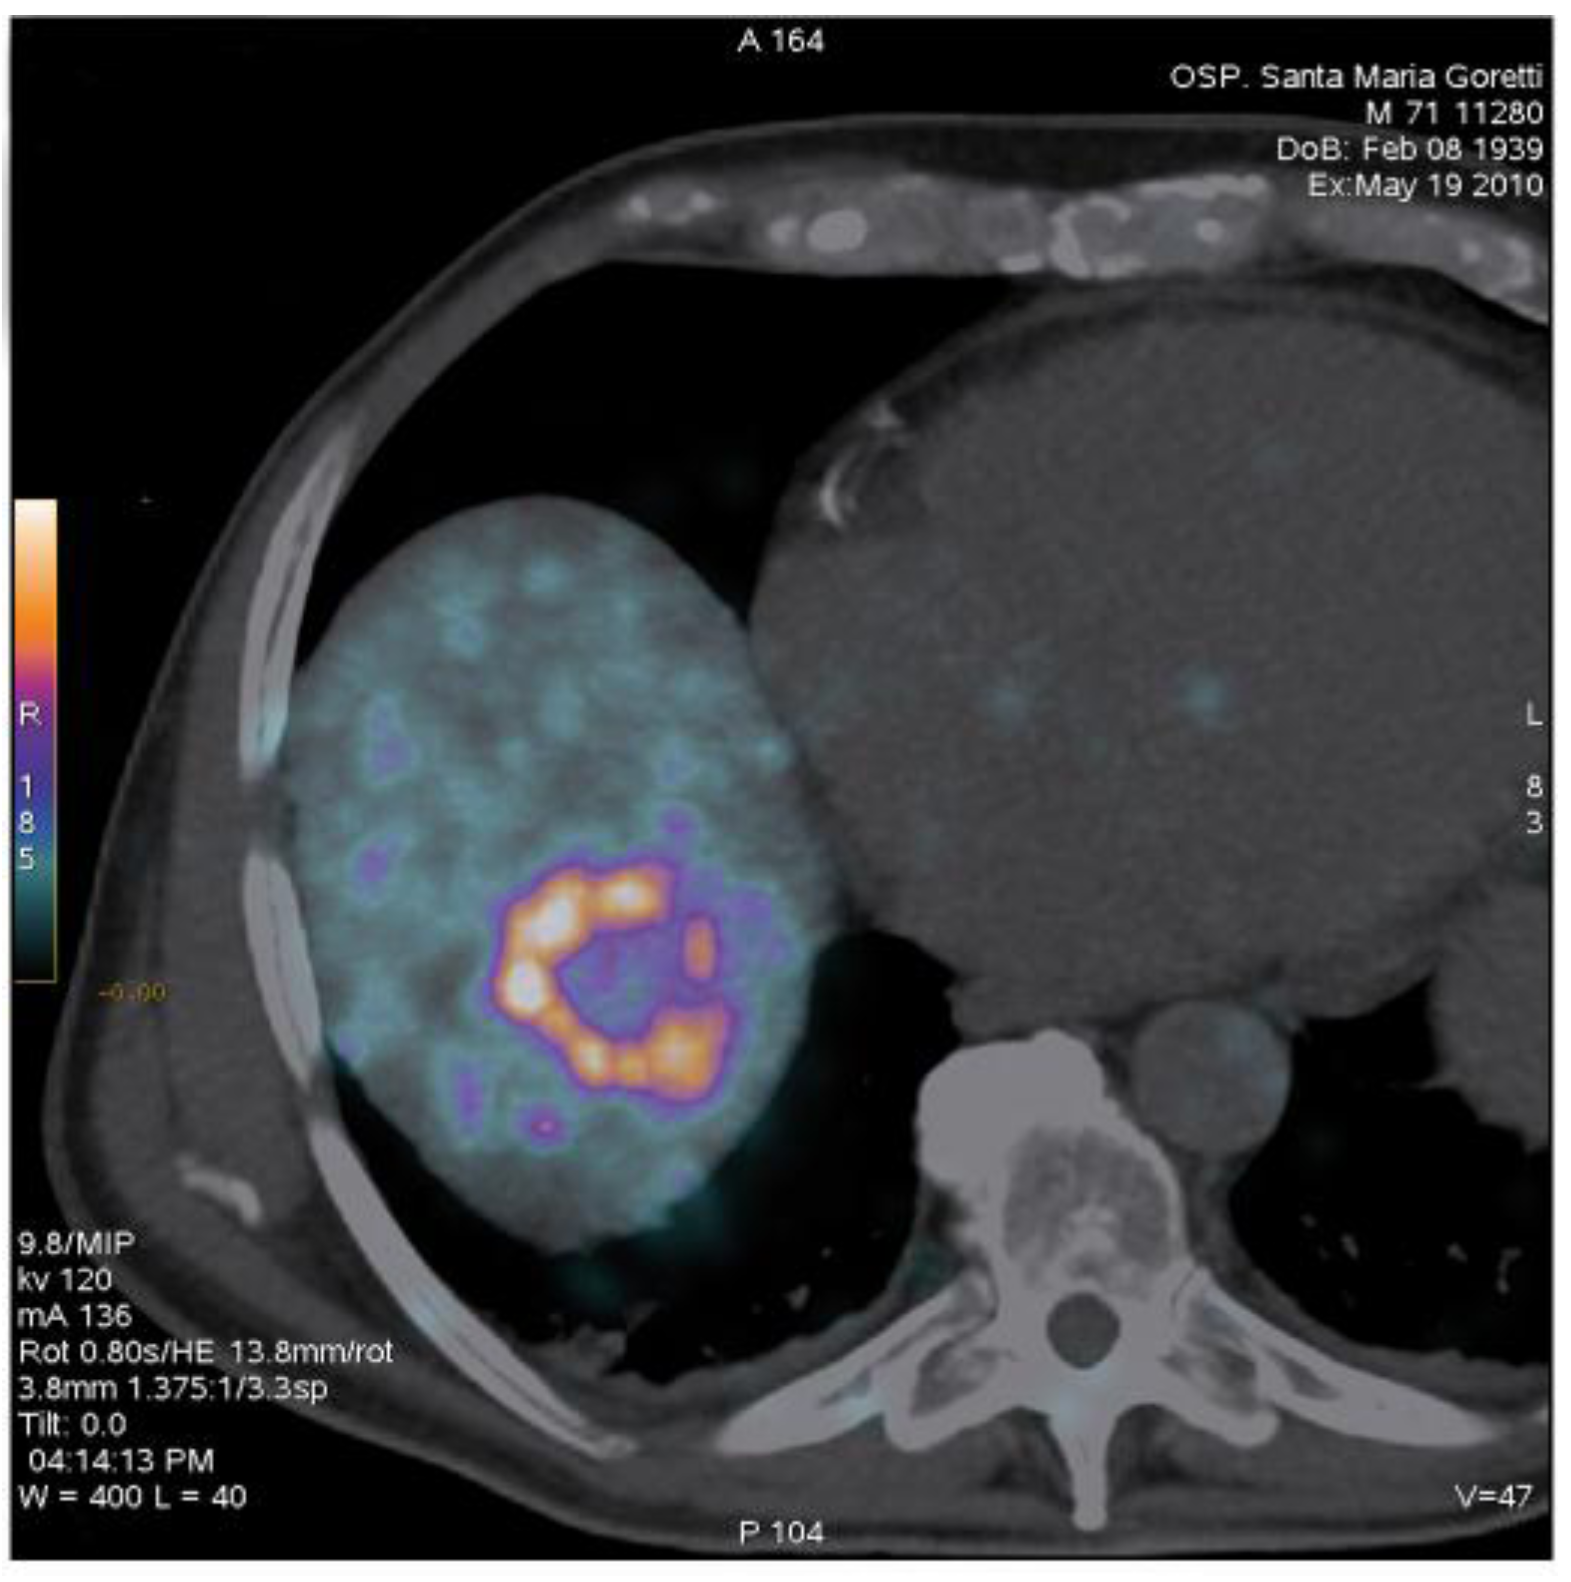

3. Exploitation in Nuclear Medicine of the β+/β–Emission from the 0+ – 0+ Transition of 90Zr

, measured by Selwyn and colleagues using a HPGe detector. Different studies indicate that the high-resolution images attainable with 90Y PET may allow for accurate patient dosimetry after locoregional administration of 90Y for therapeutic purposes. References and Notes

- Bagni, O.; D’Arienzo, M.; Chiaramida, P.; Chiacchiararelli, L.; Cannas, P.; D’Agostini, A.; Cianni, R.; Salvatori, R.; Scopinaro, F. 90Y-PET for the assessment of microsphere biodistribution after selective internal radiotherapy (SIRT). Nucl. Med. Commun. 2012, 33, 198–204. [Google Scholar] [CrossRef]

- D'Arienzo, M.; Chiaramida, P.; Chiacchiararelli, L.; Coniglio, A.; Cianni, R.; Salvatori, R.; Ruzza, A.; Scopinaro, F.; Bagni, O. 90Y PET-based dosimetry after selective internal radiotherapy treatments. Nucl. Med. Commun. 2012, 33, 633–640. [Google Scholar]